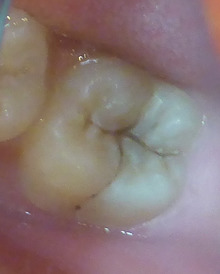

レーザーで黒い虫歯をとりました。

後は穴を樹脂で埋めます。